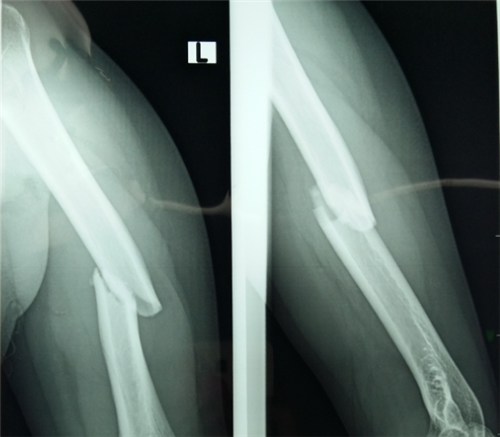

济南中德骨科医院的专家指出创伤性股骨头坏死是那些由外力撞击引起股骨颈骨折、髋关节脱位、髋关节扭挫伤等而引发的股骨头坏死,很多骨折后的患者没有得到好的治疗结果,造成了创伤性…「查看详情」

专家指出外伤,酒精,激素是导致股骨头坏死的三大常见的病因。近年来随着交通事故的频发由外伤导致的股骨头坏死逐渐的增多。那么大家对它的了解又有多少呢?众所周知创伤性股骨头坏死…「查看详情」

专家指出临床上经常出现由于骨折引起股骨头坏死的病例。那么这是什么原因呢?骨折真的会引起股骨头坏死吗?济南中德骨科医院的专家指出骨折导致股骨头坏死是有原因的,也是在一定因素…「查看详情」